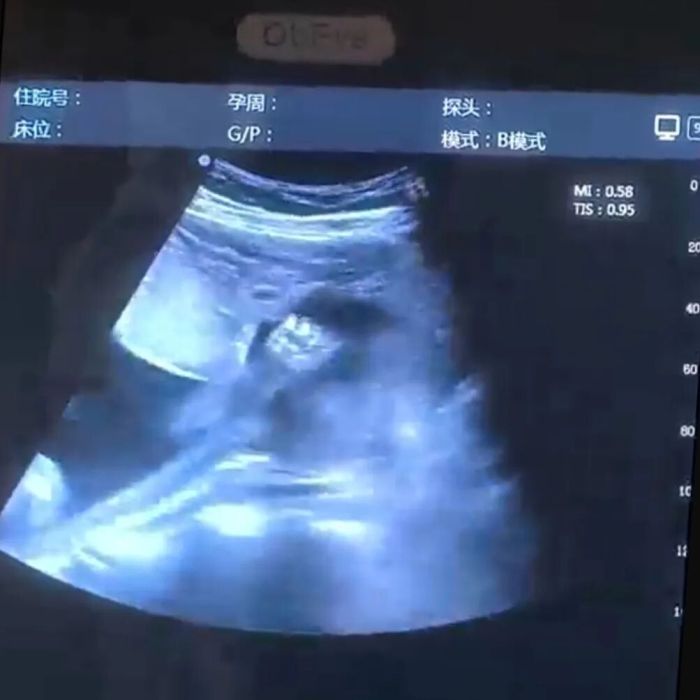

✅动态影像留存:每次检查,我们不仅解读健康(成长)数据,更会精心录制宝宝在妈妈子宫里的实时动态——翻身、吮吸、踢腿,甚至打个哈欠,都为您剪辑成专属视频。

宝宝在“跳舞”

宝宝在跟妈妈打招呼

在医生指导下,您和家属将通过高清大屏幕实时看到宝宝的一举一动。检查过程中,医生会同步讲解宝宝的发育情况,让您更懂宝宝的“悄悄话”。

检查结束后,工作人员会将录制的动态影像进行专业剪辑,配上舒缓的背景音乐,生成一段3-5分钟的“宫内成长微电影”。同时精选关键照片,排版设计成纪念册初稿。